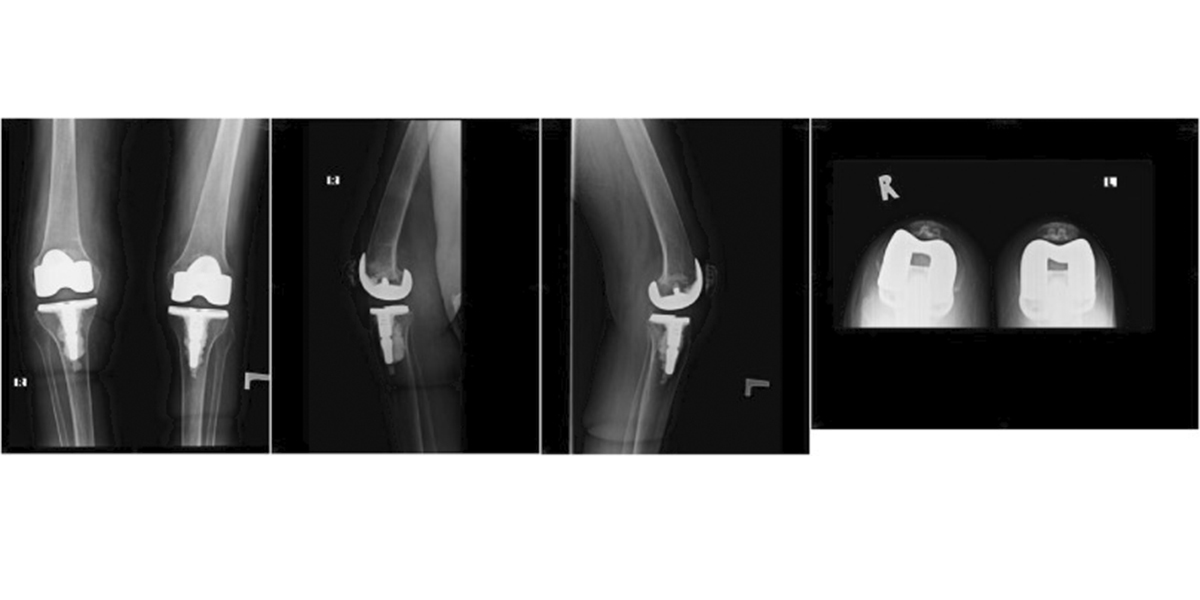

A review of five cases of fracture following TKA led Rothman Orthopaedic Institute surgeons and researchers affiliated with Hackensack Meridian Hackensack University Medical Center to recommend a shift to stemmed femoral component for certain patients with severe deformity or ligamentous instability. Their detailed findings were published in Arthroplasty Today.

The cases presented involved female patients of shorter stature and average age of 74 who underwent a primary TKA with a midlevel constraint articular surface and a primary femoral component without stem extension who all suffered isolated medial femoral condyle insufficiency fractures. Revision TKA was performed in four of the five cases.

All five patients reviewed suffered an isolated medial femoral condyle insufficiency fracture after TKA and highlight the importance for caution when using an MLC with an unstemmed femoral component in older females of shorter stature with both preoperative valgus deformity and flexion contractures. While midlevel constraint prostheses have provided increased varus/valgus and rotational stability for patients with severe deformity or ligamentous instability undergoing total knee arthroplasty (TKA), the study authors recommend considering implanting a stemmed femoral component when using a midlevel constraint articular surface in this patient population, which may help avoid fracture and revision in these particular cases. As a result of this case review, Hackensack University Medical Center orthopedic specialists now routinely consider implanting a stemmed femoral component in this population.